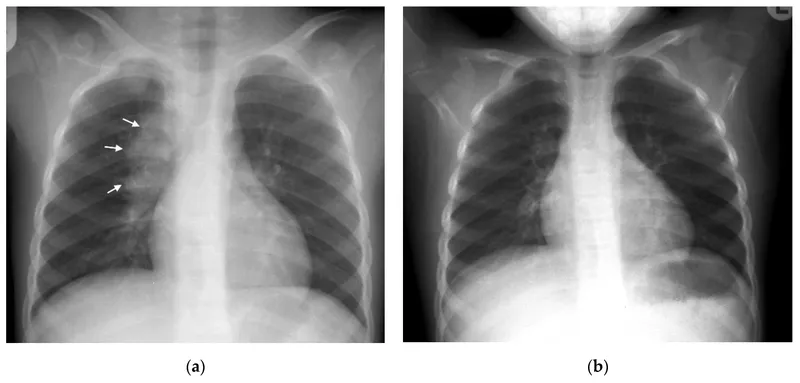

- CXR: Hilar/paratracheal lymphadenopathy is the hallmark.

- Miliary: Disseminated; "millet seed" on CXR.

- The primary complex (Ghon focus + hilar lymphadenopathy) is the most common presentation.